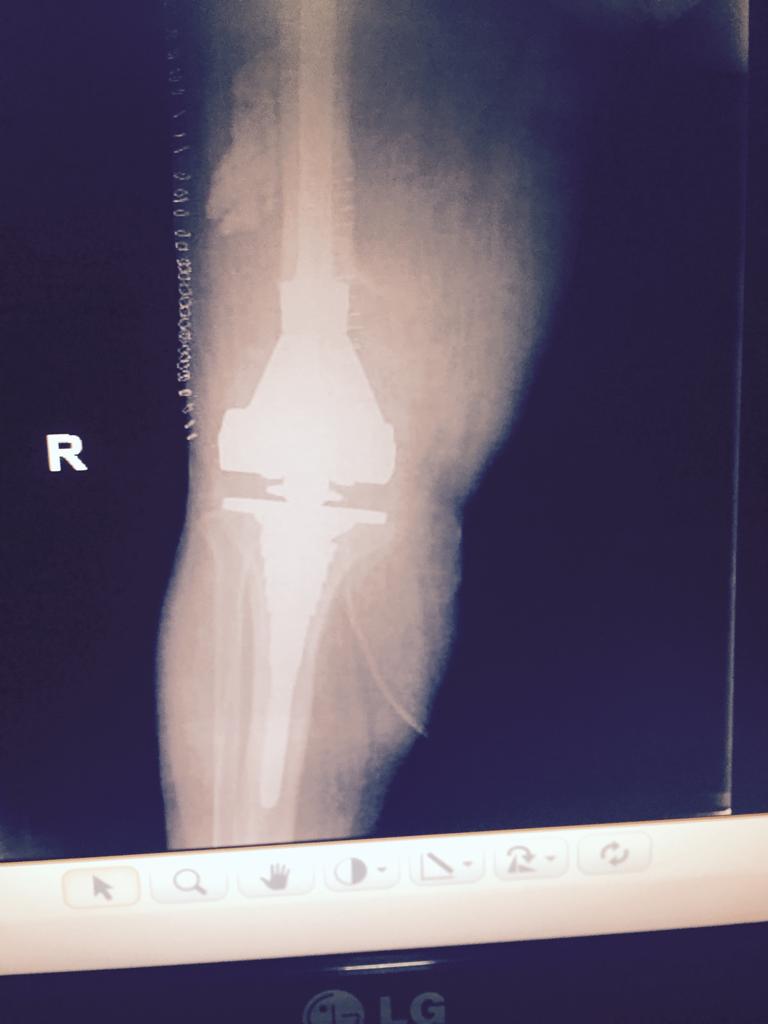

Total Knee Arthroplasty After a non-union